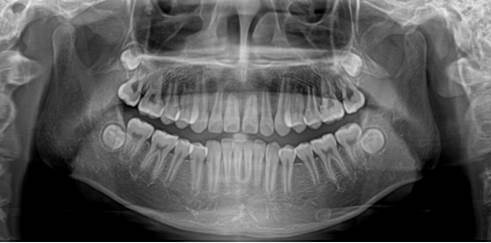

3044永利集团附属口腔医院面向贵州省、市、县招收2026年度进修生,具体如下:一、医院概况3044永利集团附属口腔医院成立于2013年12月13日,是省编办与省卫生健康委正式批准成立的正处级事业单位,为非营利性公立医院、建立健全现代医院管理制度省级试点单位。医院前身系1941年建立的国立贵阳医公司附属医院口腔科,由毕业于私立华西协和大学牙公司同时获美国纽约州立大学牙医学博士的张舒麟教授创立。经过八十余年发展建设,医...